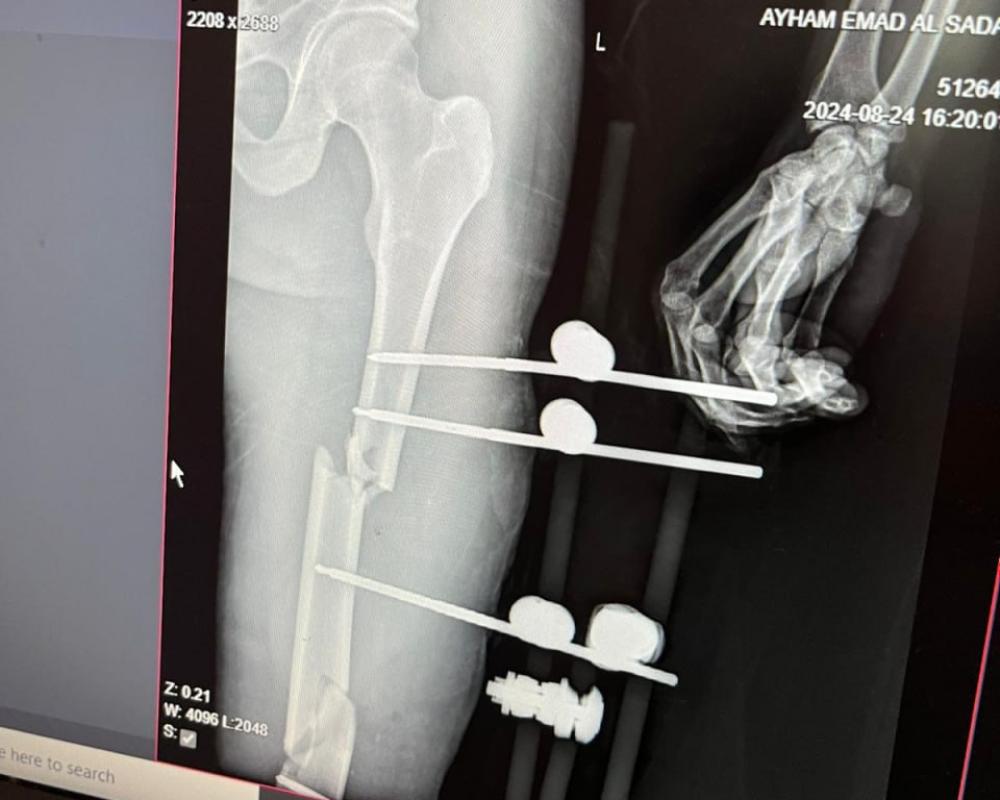

وأضاف مدير عام المستشفيات د. هيثم الهدري أن المريض كان يتلقى العلاج في غرفة عزل، ووضعه الصحي صعب، وذلك بعد أن تم إجراء 4 عمليات وتثبيت لأكثر من 7 كسور في الأطراف السفلية، وتمزق في العضلات والأربطة وتهتك للعظم، مع فقدان للأنسجة والجلد في الفخذ الأيسر، وكان لا يزال يعاني من تقرحات والتهابات حادة في منطقة العمليات إضافة  لانتشار البكتيريا داخل الدم.

وأشار الهدري إلى أن المريض يعاني من الهزال الشديد وفقدان الوزن، مؤكداً ان اختطاف المريض يشكل خطراً محدقاً على حياة هذا المريض.